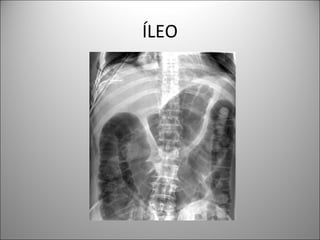

ÍLEO

• NIVELES PER SE NO INDICAN OBSTRUCCIÓN

• AUSENCIA DE NIVELES NO DESCARTA ÍLEO